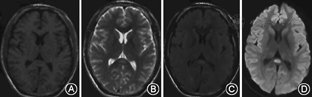

4例患者分别于发病后第1、第15、第1、第3天行MRI检查。3例MRI表现为胼胝体压部中心区孤立的类圆形病变,病变在T1WI上呈等或低信号,T2WI上呈高或稍高信号,FLAIR及DWI为高信号(图1)。1例表现为整个胼胝体压部弧形病变,同时累及双侧半卵圆中心、侧脑室旁及皮质下白质,病变在T1WI呈等信号,T2WI、FLAIR呈高信号,DWI仅可见胼胝体压部弧形高信号(图2)。

MRI显示胼胝体压部的孤立性异常信号和病灶的可逆性消失是本病主要的诊断依据。Takanashi等[7,8]根据MRI特点将MRES其分为Ⅰ型和Ⅱ型,即病灶局限于胼胝体压部的Ⅰ型和同时累及深部白质或皮质下白质的Ⅱ。本组3例患者MRI表现为胼胝体压部的孤立的类圆形病变,符合MRES分型Ⅰ型;1例表现为整个胼胝体压部受累的弧形病变,类似于"回旋镖征"[9],同时累及胼胝体外,符合Ⅱ型。Takanashi等[7]发现MRES Ⅱ型可向Ⅰ型转变,胼胝体外的异常信号可先于胼胝体压部的异常信号消失。本组1例患者MRI上DWI仅见胼胝体压部异常信号,而T2WI、FLAIR显示胼胝体及胼胝体外异常信号,推测这种不匹配的其可能的原因是患者行MRI检查是处于Ⅱ型向Ⅰ型转换的中间阶段,胼胝体外病变正逐渐消失,DWI较T2WI及FLAIR能够更敏感的显示这种改变。本研究Ⅰ型和Ⅱ型患者的临床症状及预后方面无差异,与Takanashi等[8]的报道一致。也有研究发现,胼胝体外病变的出现可能提示预后不良[10]。本组4例患者MRI病变在首次行MRI检查后4~17 d消失,患者临床症状的完全恢复晚于MRI病灶的消失。